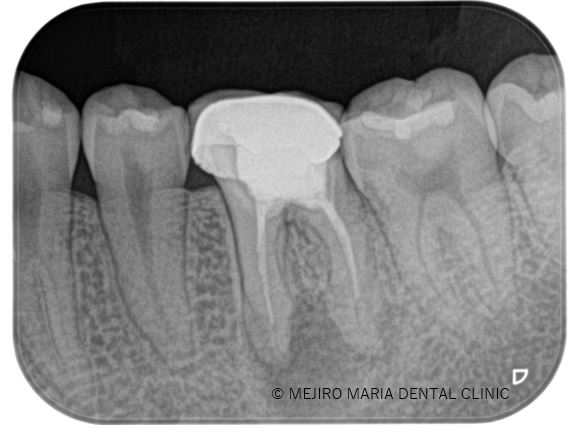

歯肉が腫れと痛みを訴え来院された患者様です。症状、レントゲン、ポケット診査より根尖性歯周炎と診断。 診査時には触ることでの痛み、限局的な歯周ポケットを確認しました。

顕微鏡下にて、軟化象牙質(虫歯)や根管内充填物を綺麗に除去し、貼薬を1週間行いました。